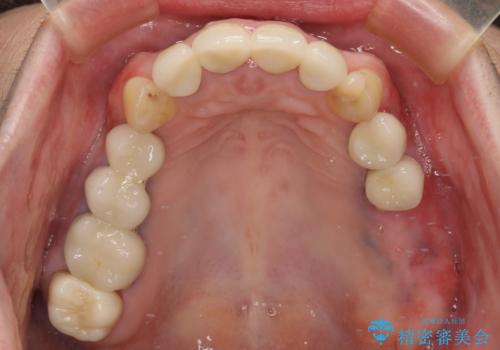

日頃の歯磨きをしっかりと行ってくださるので、新しい仮歯に変えてから速やかに歯肉の状態が改善されました。

歯肉からの出血がほとんどないため精度の良い型取りができ、非常に適合の良い補綴治療を行うことができました。